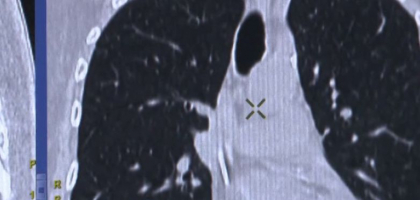

Dr. Beatrice Mahler, medic primar pneumolog: „Tuseste, expectoreaza, tranpira, pot sa aiba orice patolgie cronica. Trebuie evaluat pneumologic si facut disgnotic diferentiat cu alte afectiuni. Primul diagnostic care trebuie exclus este tuberculoza.”

Boala apare cand apararea imunitara e deficitara. Ca sa fie contagioasa, trebuie sa stati in imediata apropiere a unui pacient care are leziuni extinse in plamani, adica un pacient care nu stie de boala si nici nu o trateaza.